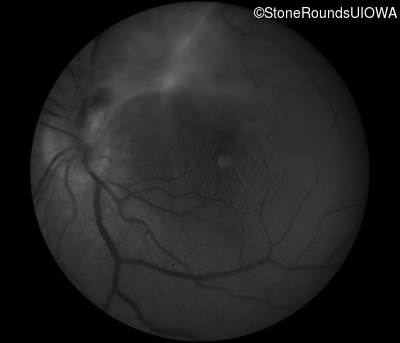

Fluorescein Angiography - Right - 20/50 -1 sc

Exemplar